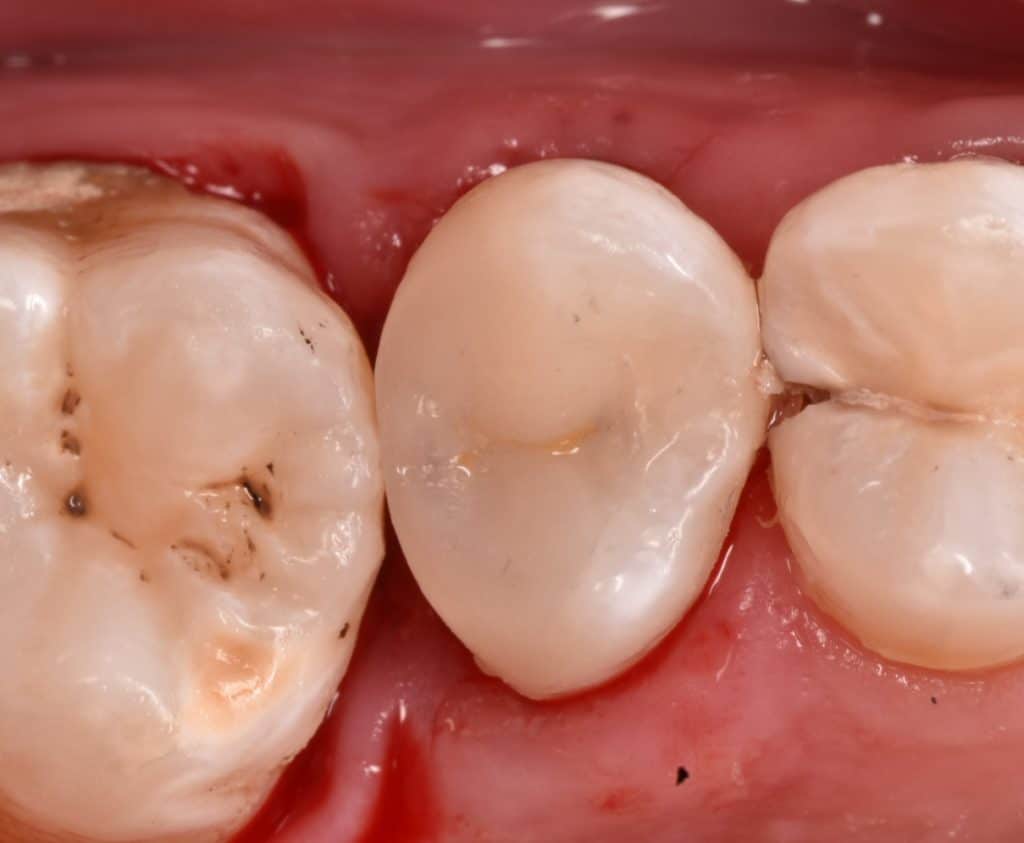

Converted to Cl l cavity

Palatal view

Ever x posterior for dentin replacement , strengthen the filling and can stop cracks

Immediate result